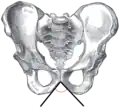

Angle sous-pubien masculin